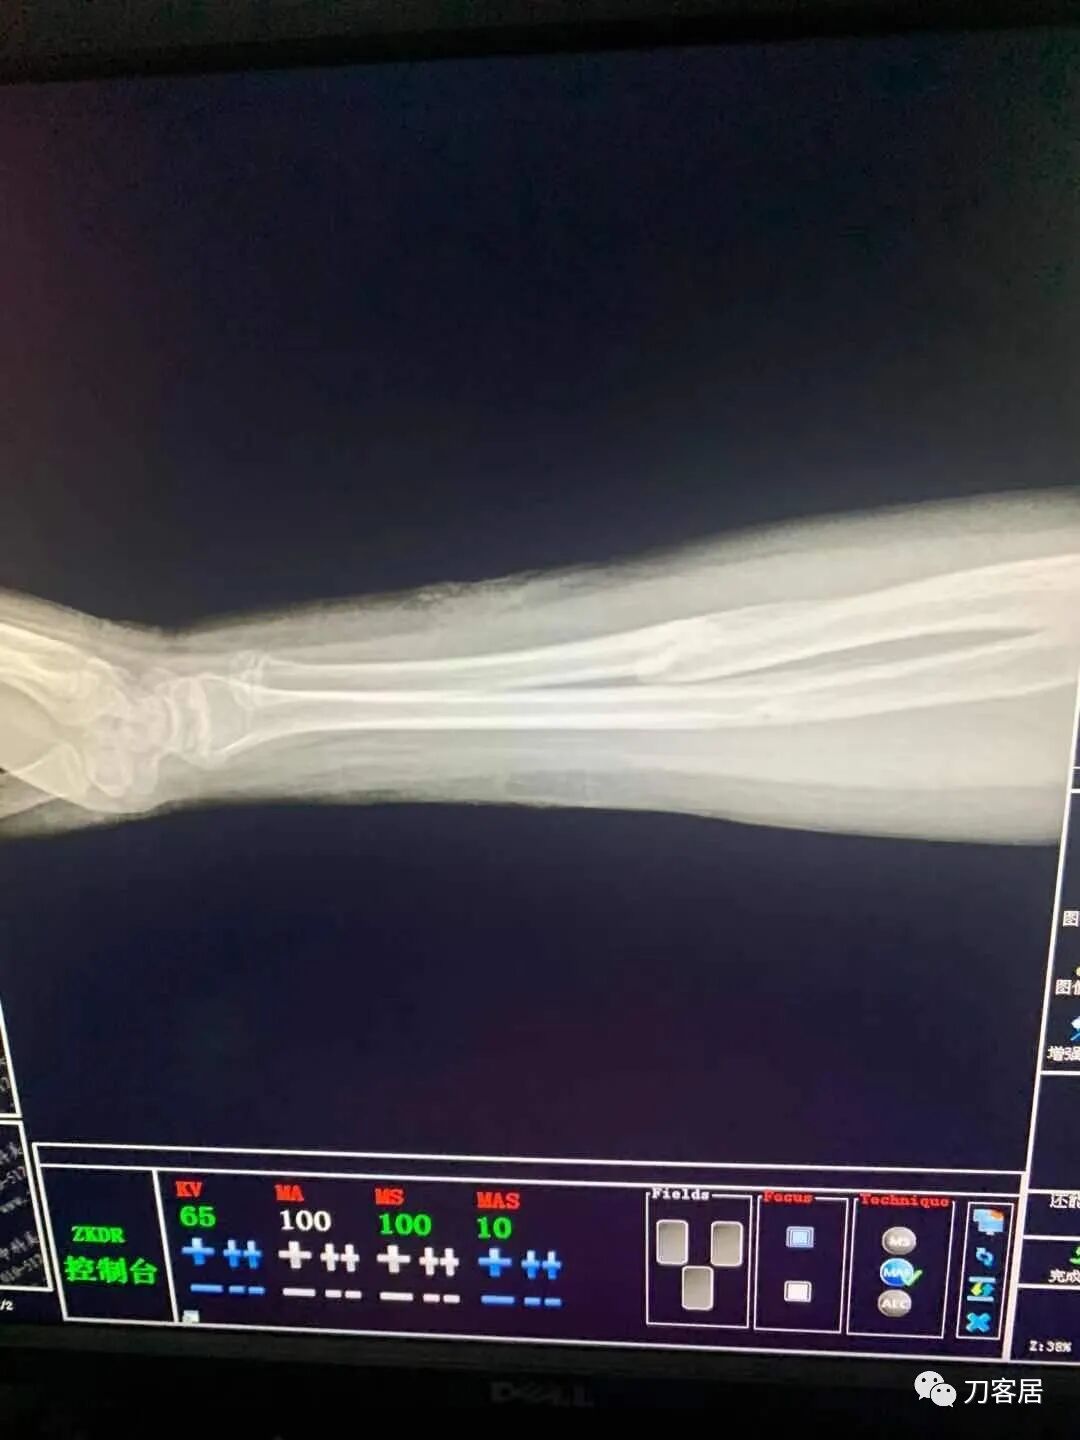

下面是这个6岁孩子,尺桡骨远端双骨折的术前及术后片子和外观照片。

2.  这个骨折处理起来也很简单,单纯的打石膏托或者中医的小夹板,或者正规的包括腕关节和肘关节的管型石膏外固定4周即可治愈该骨折。实在不行,如果这个孩子比较听话,不太调皮的话,用一本书,一个三角巾悬吊固定4周,都可以治愈该骨折。但是给这个患者用外固定架做了手术,而且桡骨远端的几颗克氏针距离骨折线太近,其中一枚克氏针进入到骨折间隙内。从这个术中图片来看,术者的外固定手术技术也有待于进一步的提高。毕竟术者应该还很年轻。从X线片来看,前臂及手的尺侧有不透光影,应该还使用了外固定石膏绷带托,而且我猜测应该是高分子的石膏绷带托,这个是纯属猜测,不一定是对的,不过如何解释前臂尺侧的不透光影呢?如果真是用了石膏绷带外固定的话,那为啥要做手术呢?外固定架术后就不该再用石膏绷带托辅助了。